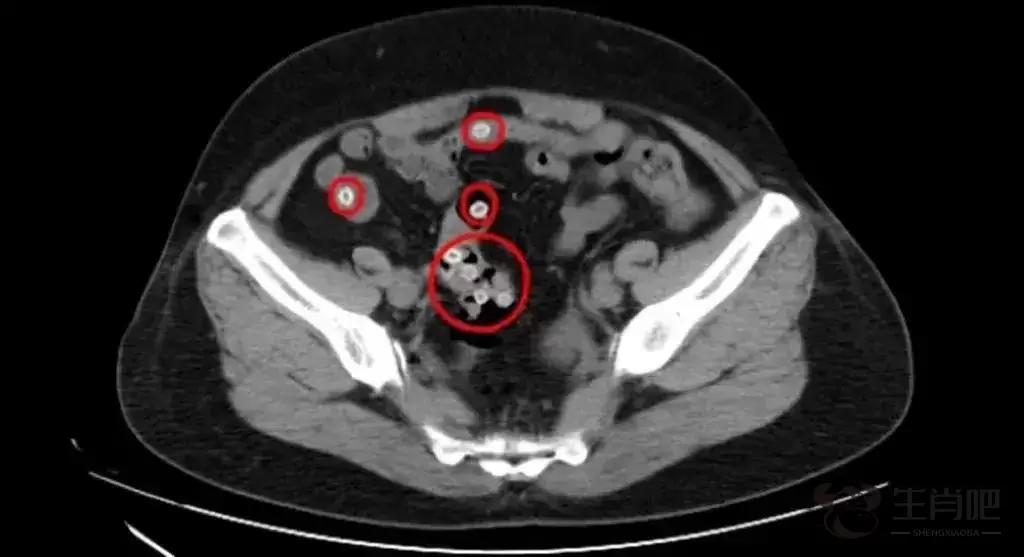

△CT影像显示,患者肠道内有不少杨梅核滞留

CT影像显示,王阿姨的肠内存在多处类圆形高密度影,密密麻麻的圆圆小白点正是滞留在肠道内的杨梅核,这是导致患者腹痛不止的罪魁祸首。